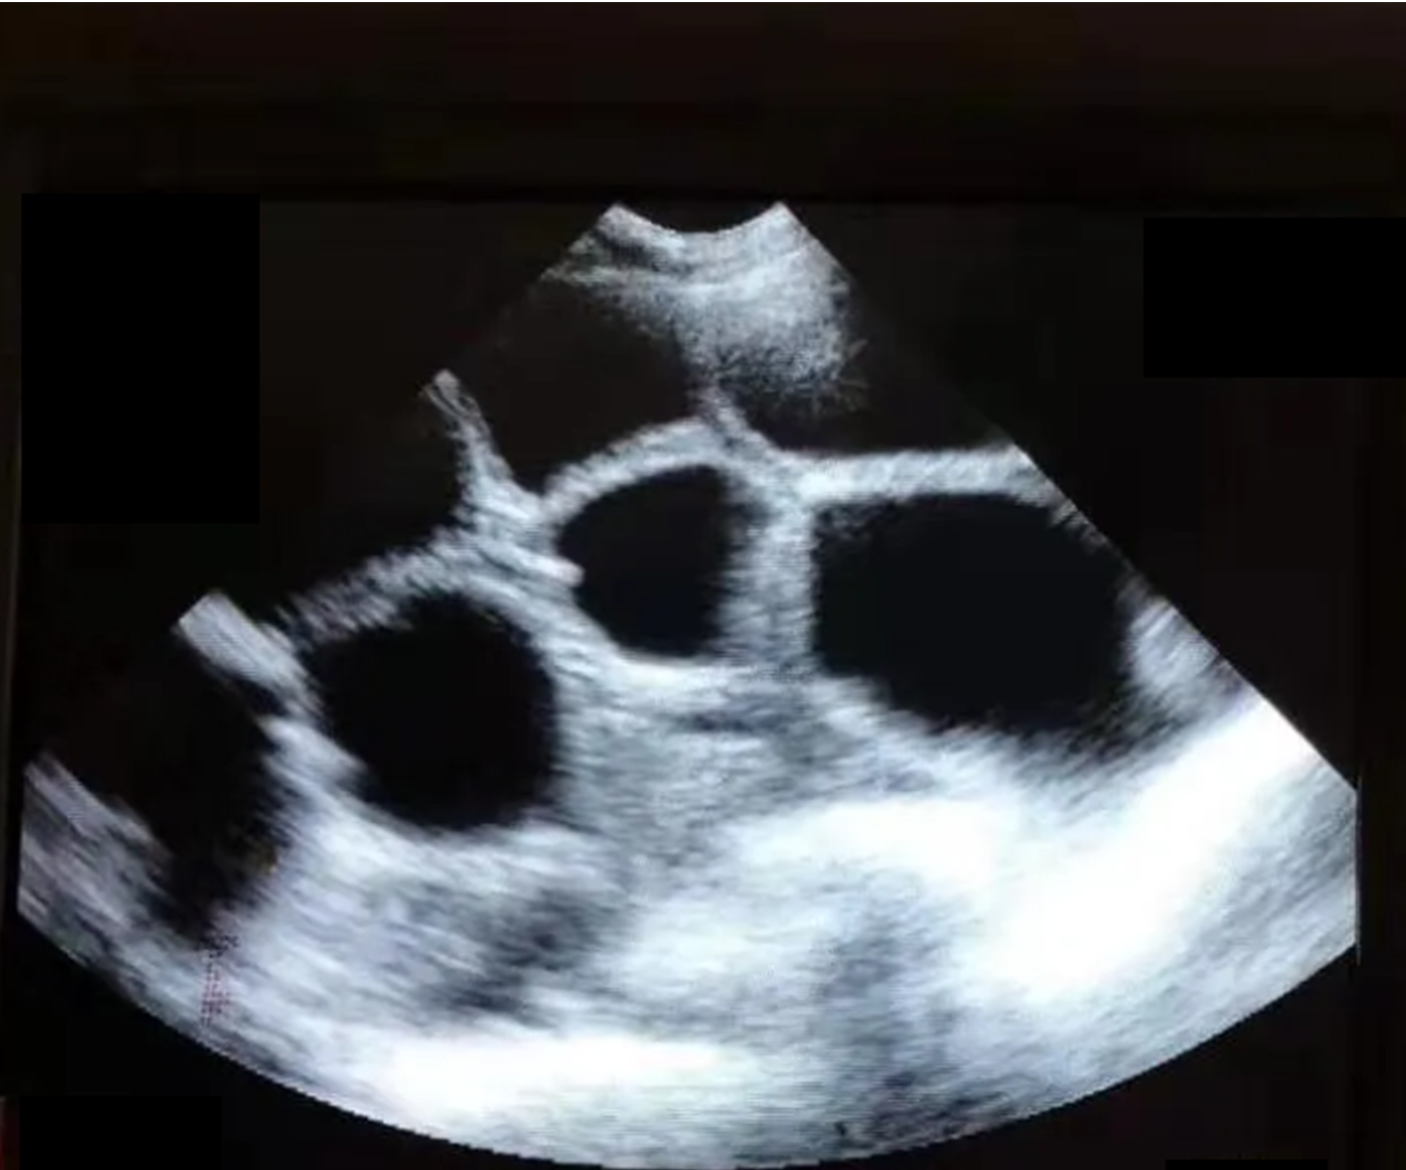

第四步:在 B 超仪探头顶端均匀涂抹适量耦合剂,将探头紧贴母猪皮肤,轻轻施加压力,缓慢向前、向后或向侧面转动探头,直至屏幕显示清晰的妊娠图像(如可见孕囊、胚胎等特征)。

第五步:若单侧检测未获得清晰图像,需在另一侧重复上述操作;若两侧均无法获得清晰图像,立即为该母猪做好标记,等待复检。